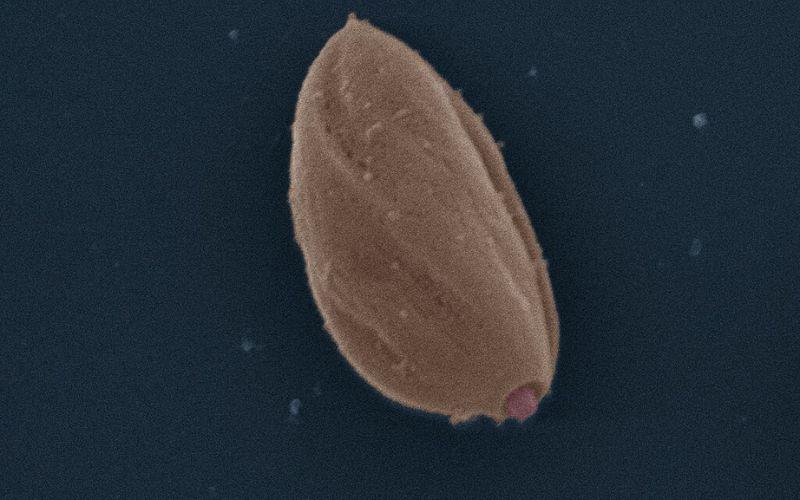

- Amastigota. Constituye la forma replicativa. Es redondeada u ovalada, con un diámetro que oscila entre 2 y 5 μm. Carece de flagelo.

– Morfología. Es un protozoo unicelular flagelado con dos formas principales en su ciclo biológico: 1) promastigote: se encuentra en el intestino del vector (mosquito flebótomo). Es alargado, con un flagelo libre anterior que le da movilidad. Mide aproximadamente 15-20 µm de largo. 2) Amastigote: se encuentra dentro de las células del hospedador vertebrado (macrófagos). Es ovalado o redondeado, sin flagelo libre, y mide 2-4 µm.